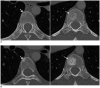

Tumor response may be assessed readily by the use of Response Evaluation Criteria in Solid Tumor version 1.1. However, the criteria mainly depend on tumor size changes. These criteria do not reflect other morphologic (tumor necrosis, hemorrhage, and cavitation), functional, or metabolic changes that may occur with targeted chemotherapy or even with conventional chemotherapy. The state-of-the-art multidetector CT is still playing an important role, by showing high-quality, high-resolution images that are appropriate enough to measure tumor size and its changes. Additional imaging biomarker devices such as dual energy CT, positron emission tomography, MRI including diffusion-weighted MRI shall be more frequently used for tumor response evaluation, because they provide detailed anatomic, and functional or metabolic change information during tumor treatment, particularly during targeted chemotherapy. This review elucidates morphologic and functional or metabolic approaches, and new concepts in the evaluation of tumor response in the era of personalized medicine (targeted chemotherapy).